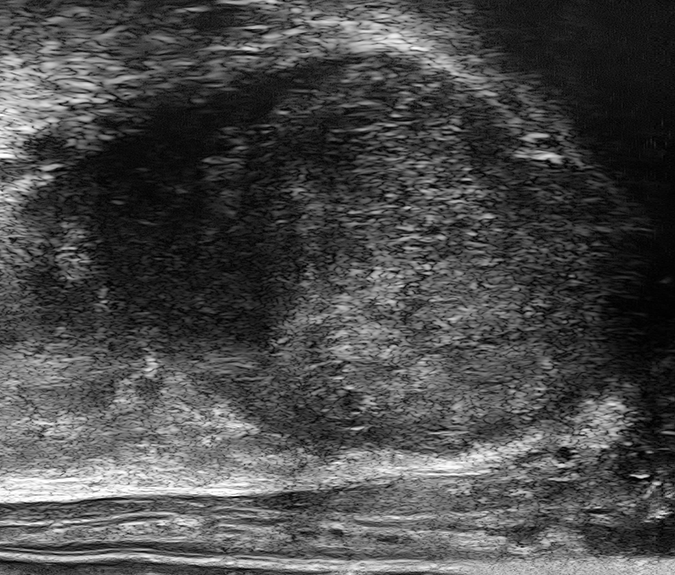

PRI-MUS 1

Small regular ducts "Swiss Cheese"